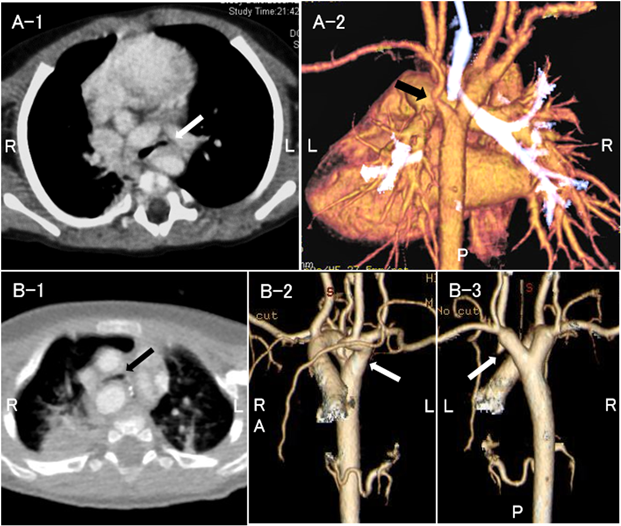

症例4以外の全例に造影CTを行い,心血管構造による気管気管支の圧排,扁平化を認めたため,外的圧迫による二次性気管気管支軟化症と診断した.先天性気管狭窄の症例はなかった.各群の代表的な画像をFig. 1に例示した.I群は主に拡大した肺動脈,II群は拡大した肺動脈や左房,III群は血管輪を形成する大動脈弓や動脈管索等で気管気管支を圧排されていた.症例14は右大動脈弓,Kommerell憩室を伴う左鎖骨下動脈起始異常で血管輪を形成し,左主気管支が主に圧排されていた(Fig. 2A).症例15は右大動脈弓,Kommerell憩室を伴う左腕頭動脈起始異常で非常に稀な血管奇形であった8).造影CTおよび心臓手術の術中所見で左総頸動脈・左鎖骨下動脈と上行大動脈との連続性がなかったことから確定診断した(Fig. 2B).

Fig. 1 Computed tomographic and esophagraphic images of typical cases from each group

A: Case 5 at birth (group I). The left pulmonary artery is markedly enlarged (black arrow). The bronchi are not visible (white arrow) because of compression of the tracheal bifurcation. B: Case 8 at 3 months of age (group II). The dilated right pulmonary artery compressed the trachea (black arrow). The tracheal bifurcation is flattened (white arrow). C: Case 11 at 4 months of age (group III). The trachea is compressed by the right aortic arch in the vascular ring (white arrow). The esophagram demonstrates posterior esophageal indentation (black arrow).